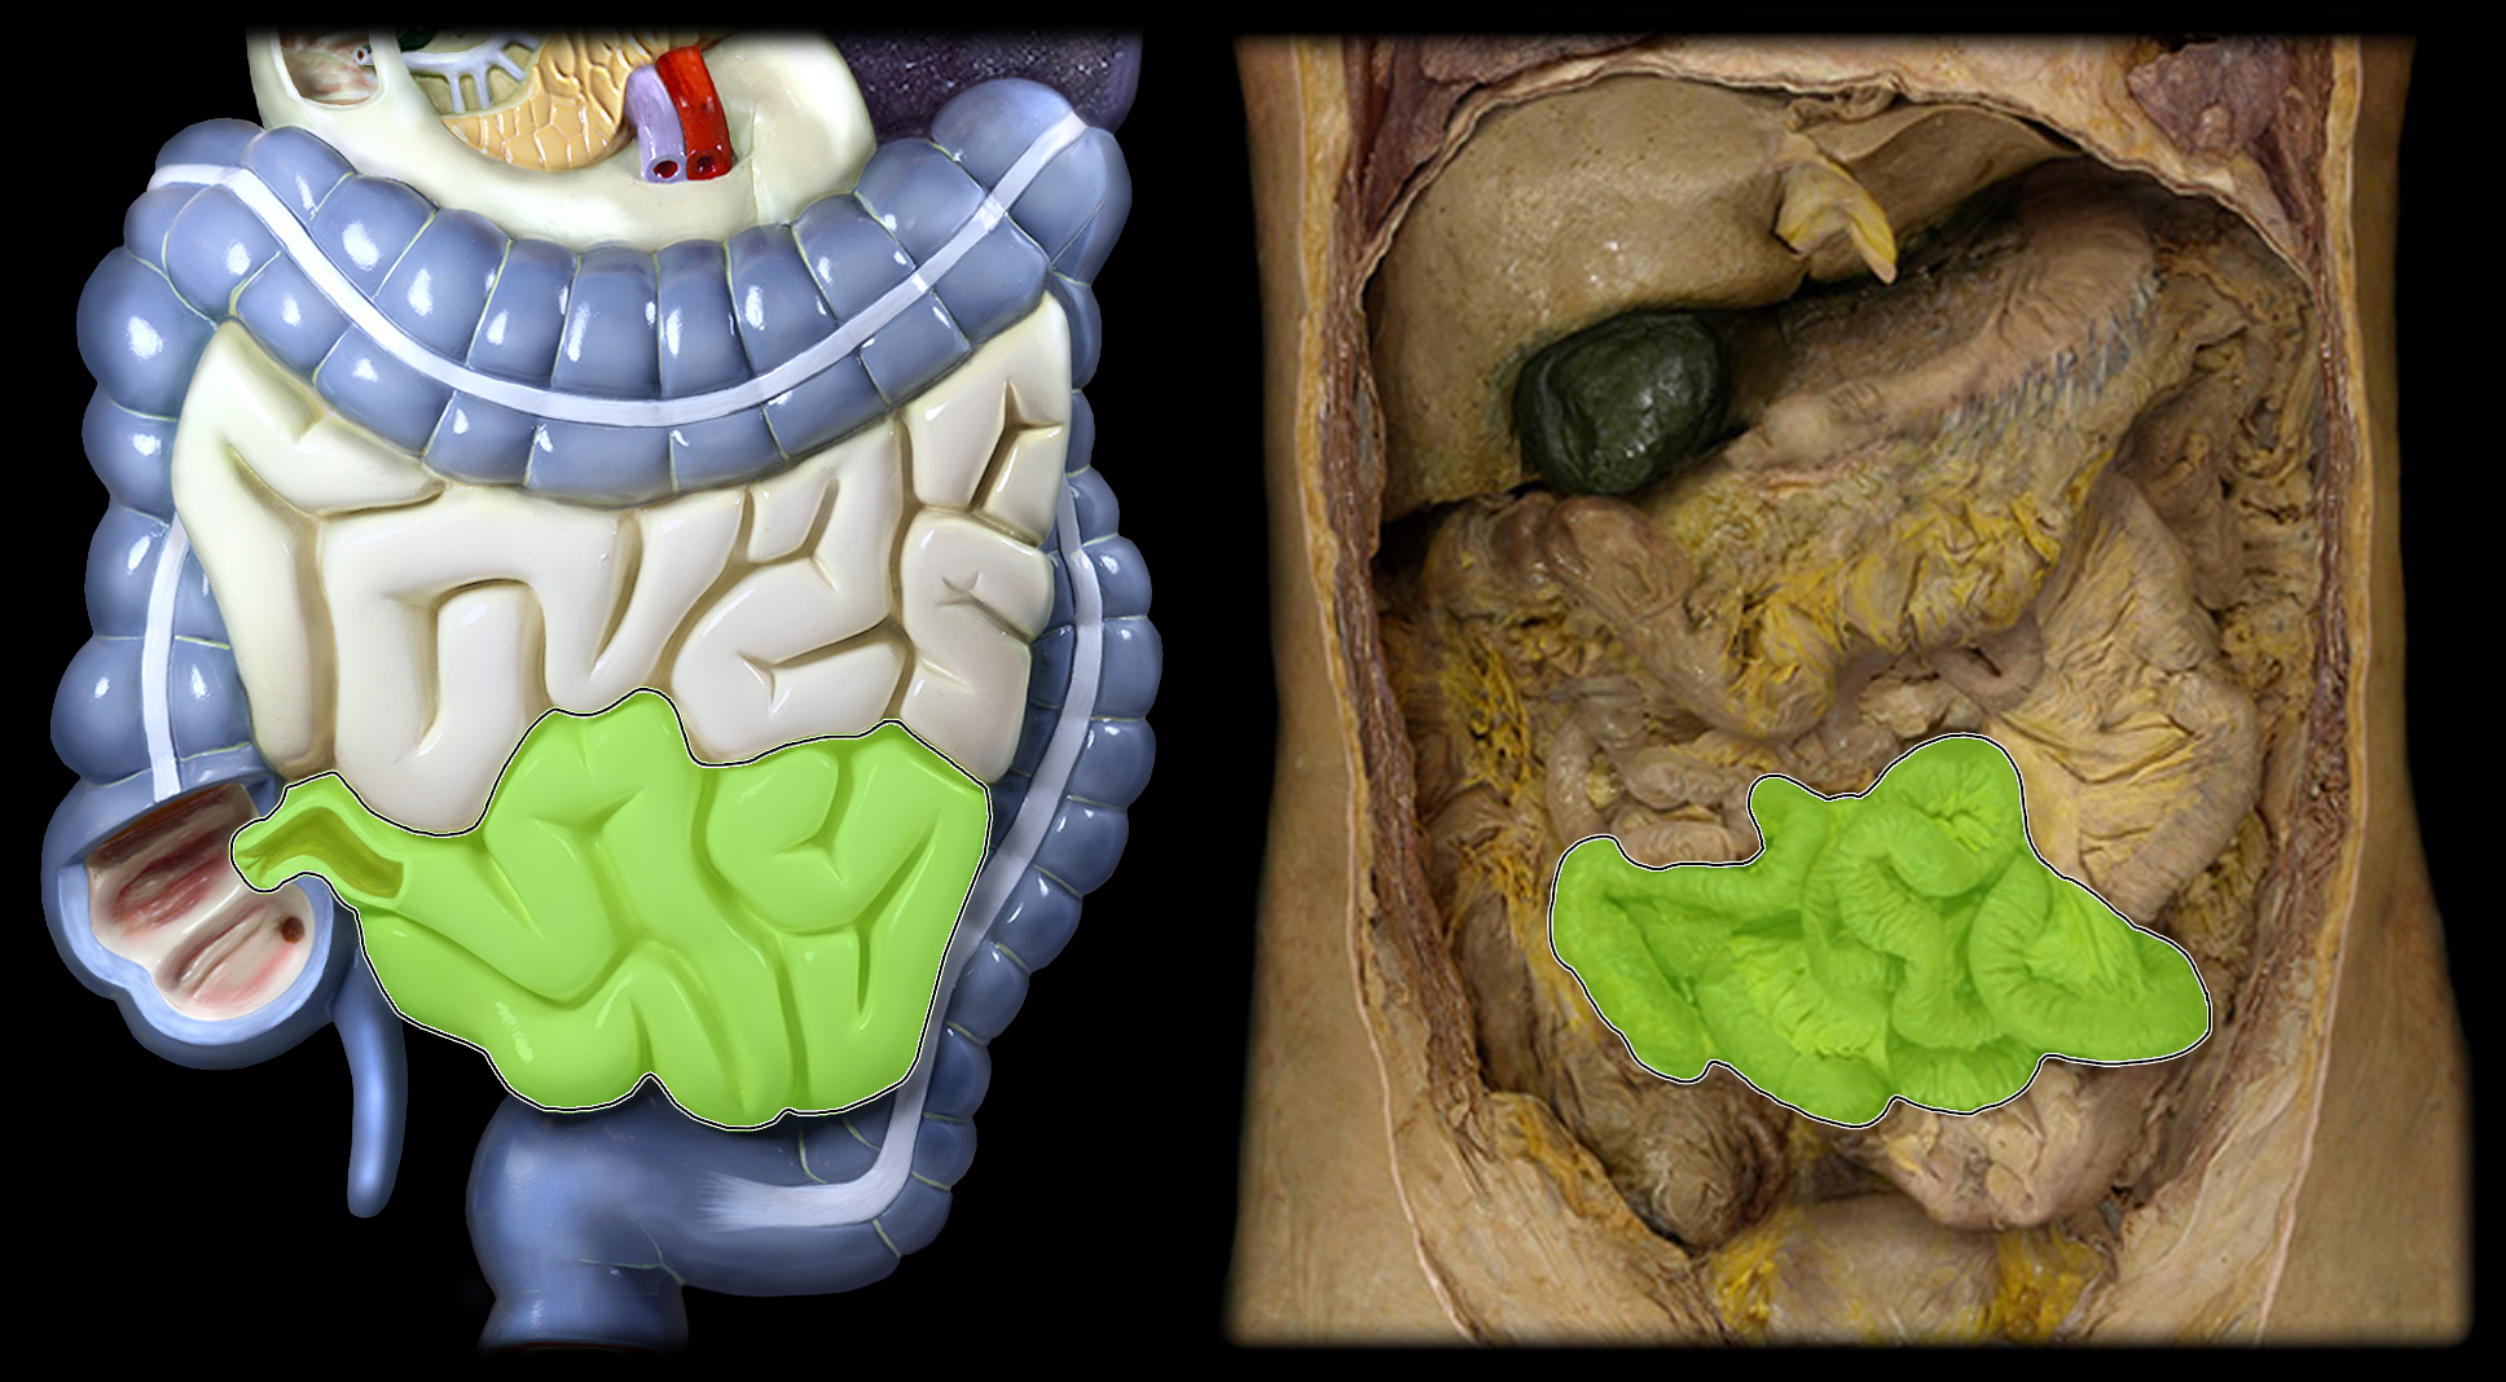

Jejunum

Ileum